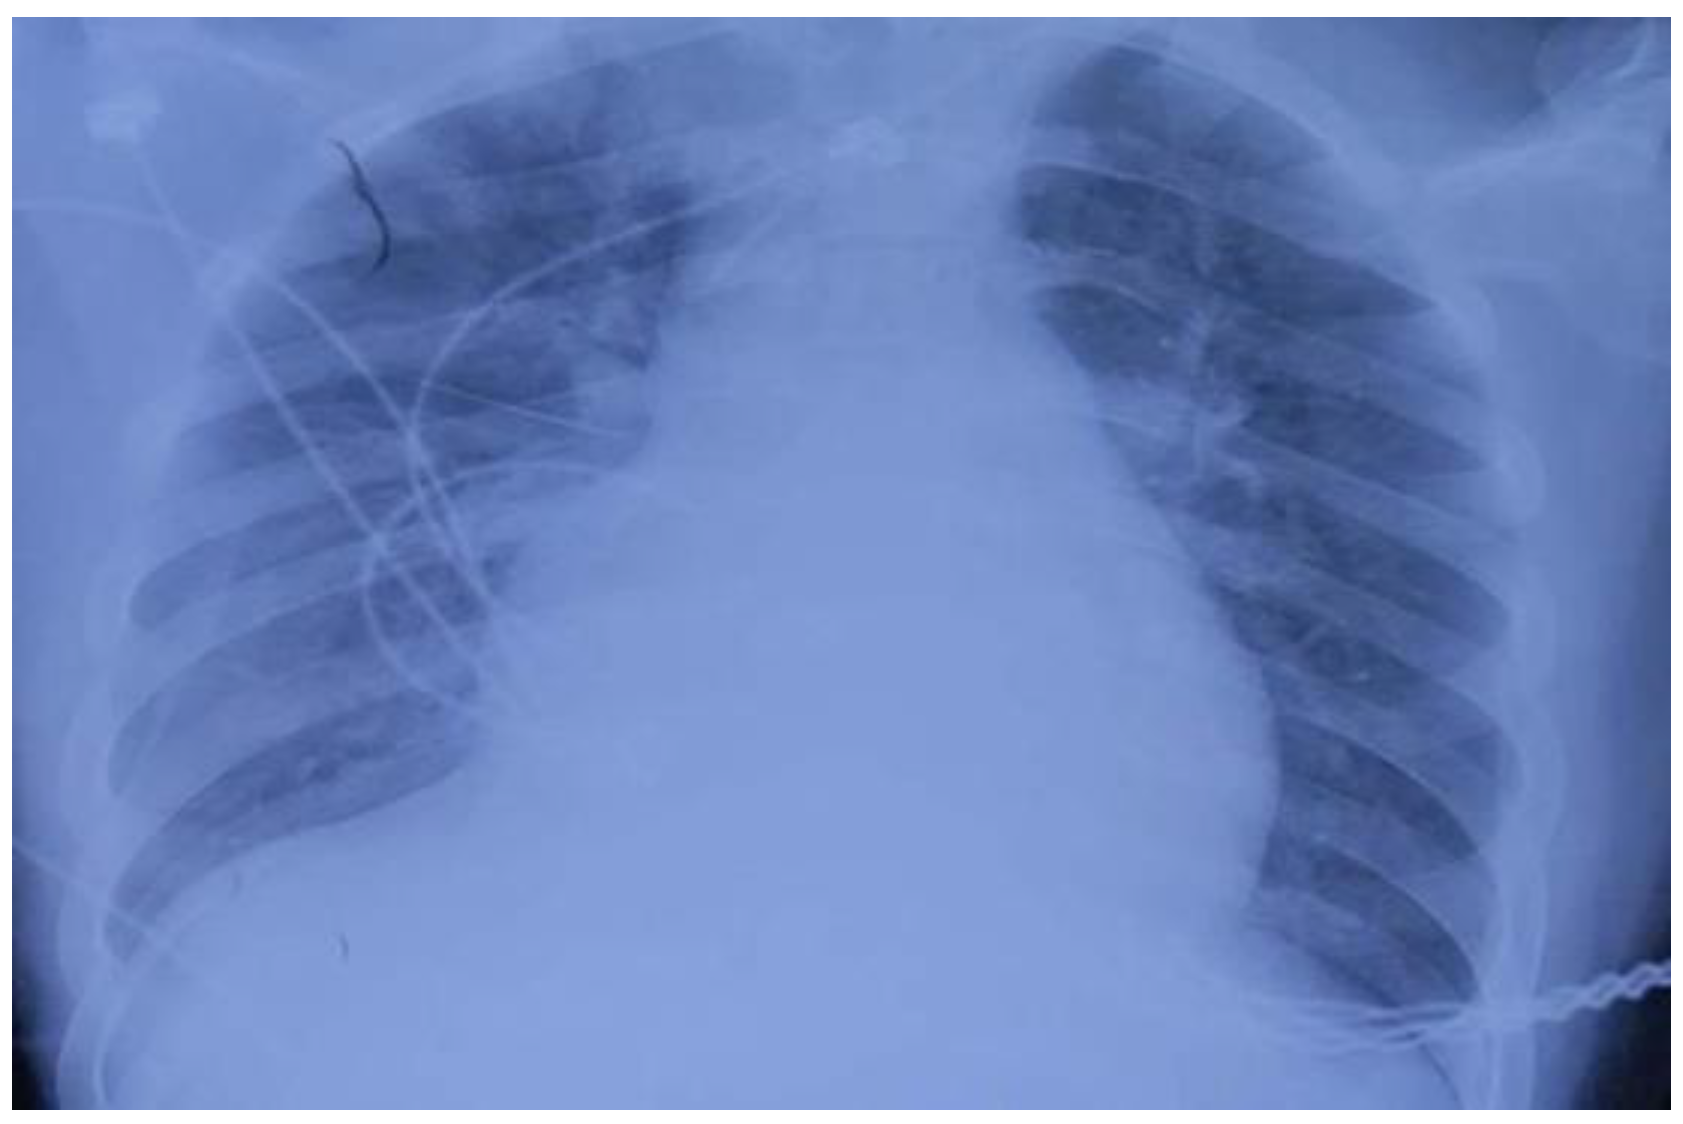

On 22 July, a 15-year-old male patient, approximately 173 cm in height and 80 kg in weight, went to a local hospital for treatment with nausea and chest tightness as the main symptoms. Routine blood tests, liver and kidney function tests, and an electrocardiogram were performed. The patient underwent no special treatment and was sent back home. On 23 July, while performing fumigation of the granary, the patient suddenly lost consciousness and was foaming at the mouth. He was taken back to the local hospital where he entered a coma and received endotracheal intubation as well as ventilator-assisted respiration. The local hospital administered IV fluids with diuretics for rehydration and to prevent fluid overload, respectively. Further imaging using bedside chest radiography (Figure 1) and an electrocardiogram were performed. Thereafter, the patient was transferred to the intensive care unit at 18:45 for intermittent hemoperfusion. Epinephrine and norepinephrine were continuously administered, and blood pressure was maintained at 120/70 mmHg. On 25 July, results from the local hospital showed a glutamic pyruvic transaminase level of 2934 U/L; glutamic oxaloacetic transaminase, 1870 U/L; total bilirubin, 30.7 μmol/L; and indirect bilirubin, 25.7 μmol/L. Further, on 26 July, the glutamic pyruvic transaminase level was 2536 U/L and the glutamic oxaloacetic transaminase level was 857 U/L. For further treatment, the patient’s family members transferred him to our hospital. The patient was located at Bozhou People’s Hospital in Anhui Province, which is more than 400 km away from us. After more than 4 h of ambulance transport, the patient arrived at our hospital at 9:00 a.m. on 27 July, and still required continuous instrumental ventilation.

Figure 1.

Bedside chest radiographs performed on 24 July 2018, showing extensive ground-glass changes in the right lung, exudate changes in both lungs, and an enlarged heart boundary.